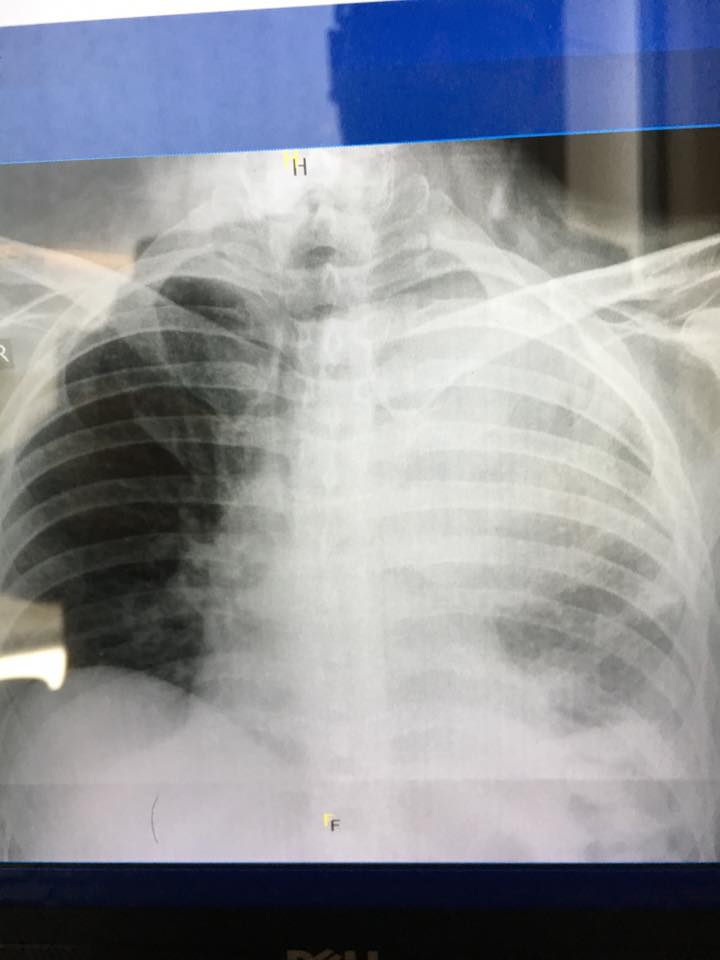

«Αυτές είναι φωτογραφίες από μερικούς καρκινοπαθείς ασθενείς μου.

Με την άδεια του Γιώργου Άστρα, ο οποίος είναι ένα από τα μέλη της εξειδικευμένης επιστημονικής ομάδας της Ογκολογικής Μονάδας στο American Medical Center, αναδημοσιεύουμε τις φωτογραφίες, ενώ παραθέτουμε και μια συμπληρωματική δήλωση του στη CITY:

Δείτε τις πραγματικά συγκλονιστικές φωτογραφίες: